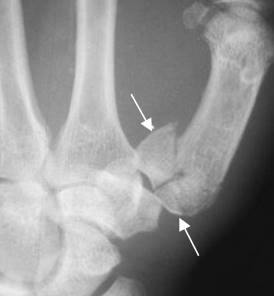

Fig 175 B. Luxofractura de Bennet.

A: Rx AP y B: Rx oblicua. Subluxación de la articulación carpometacarpiana del pulgar y fractura en la base del metacarpiano, por luxofractura de Bennet.